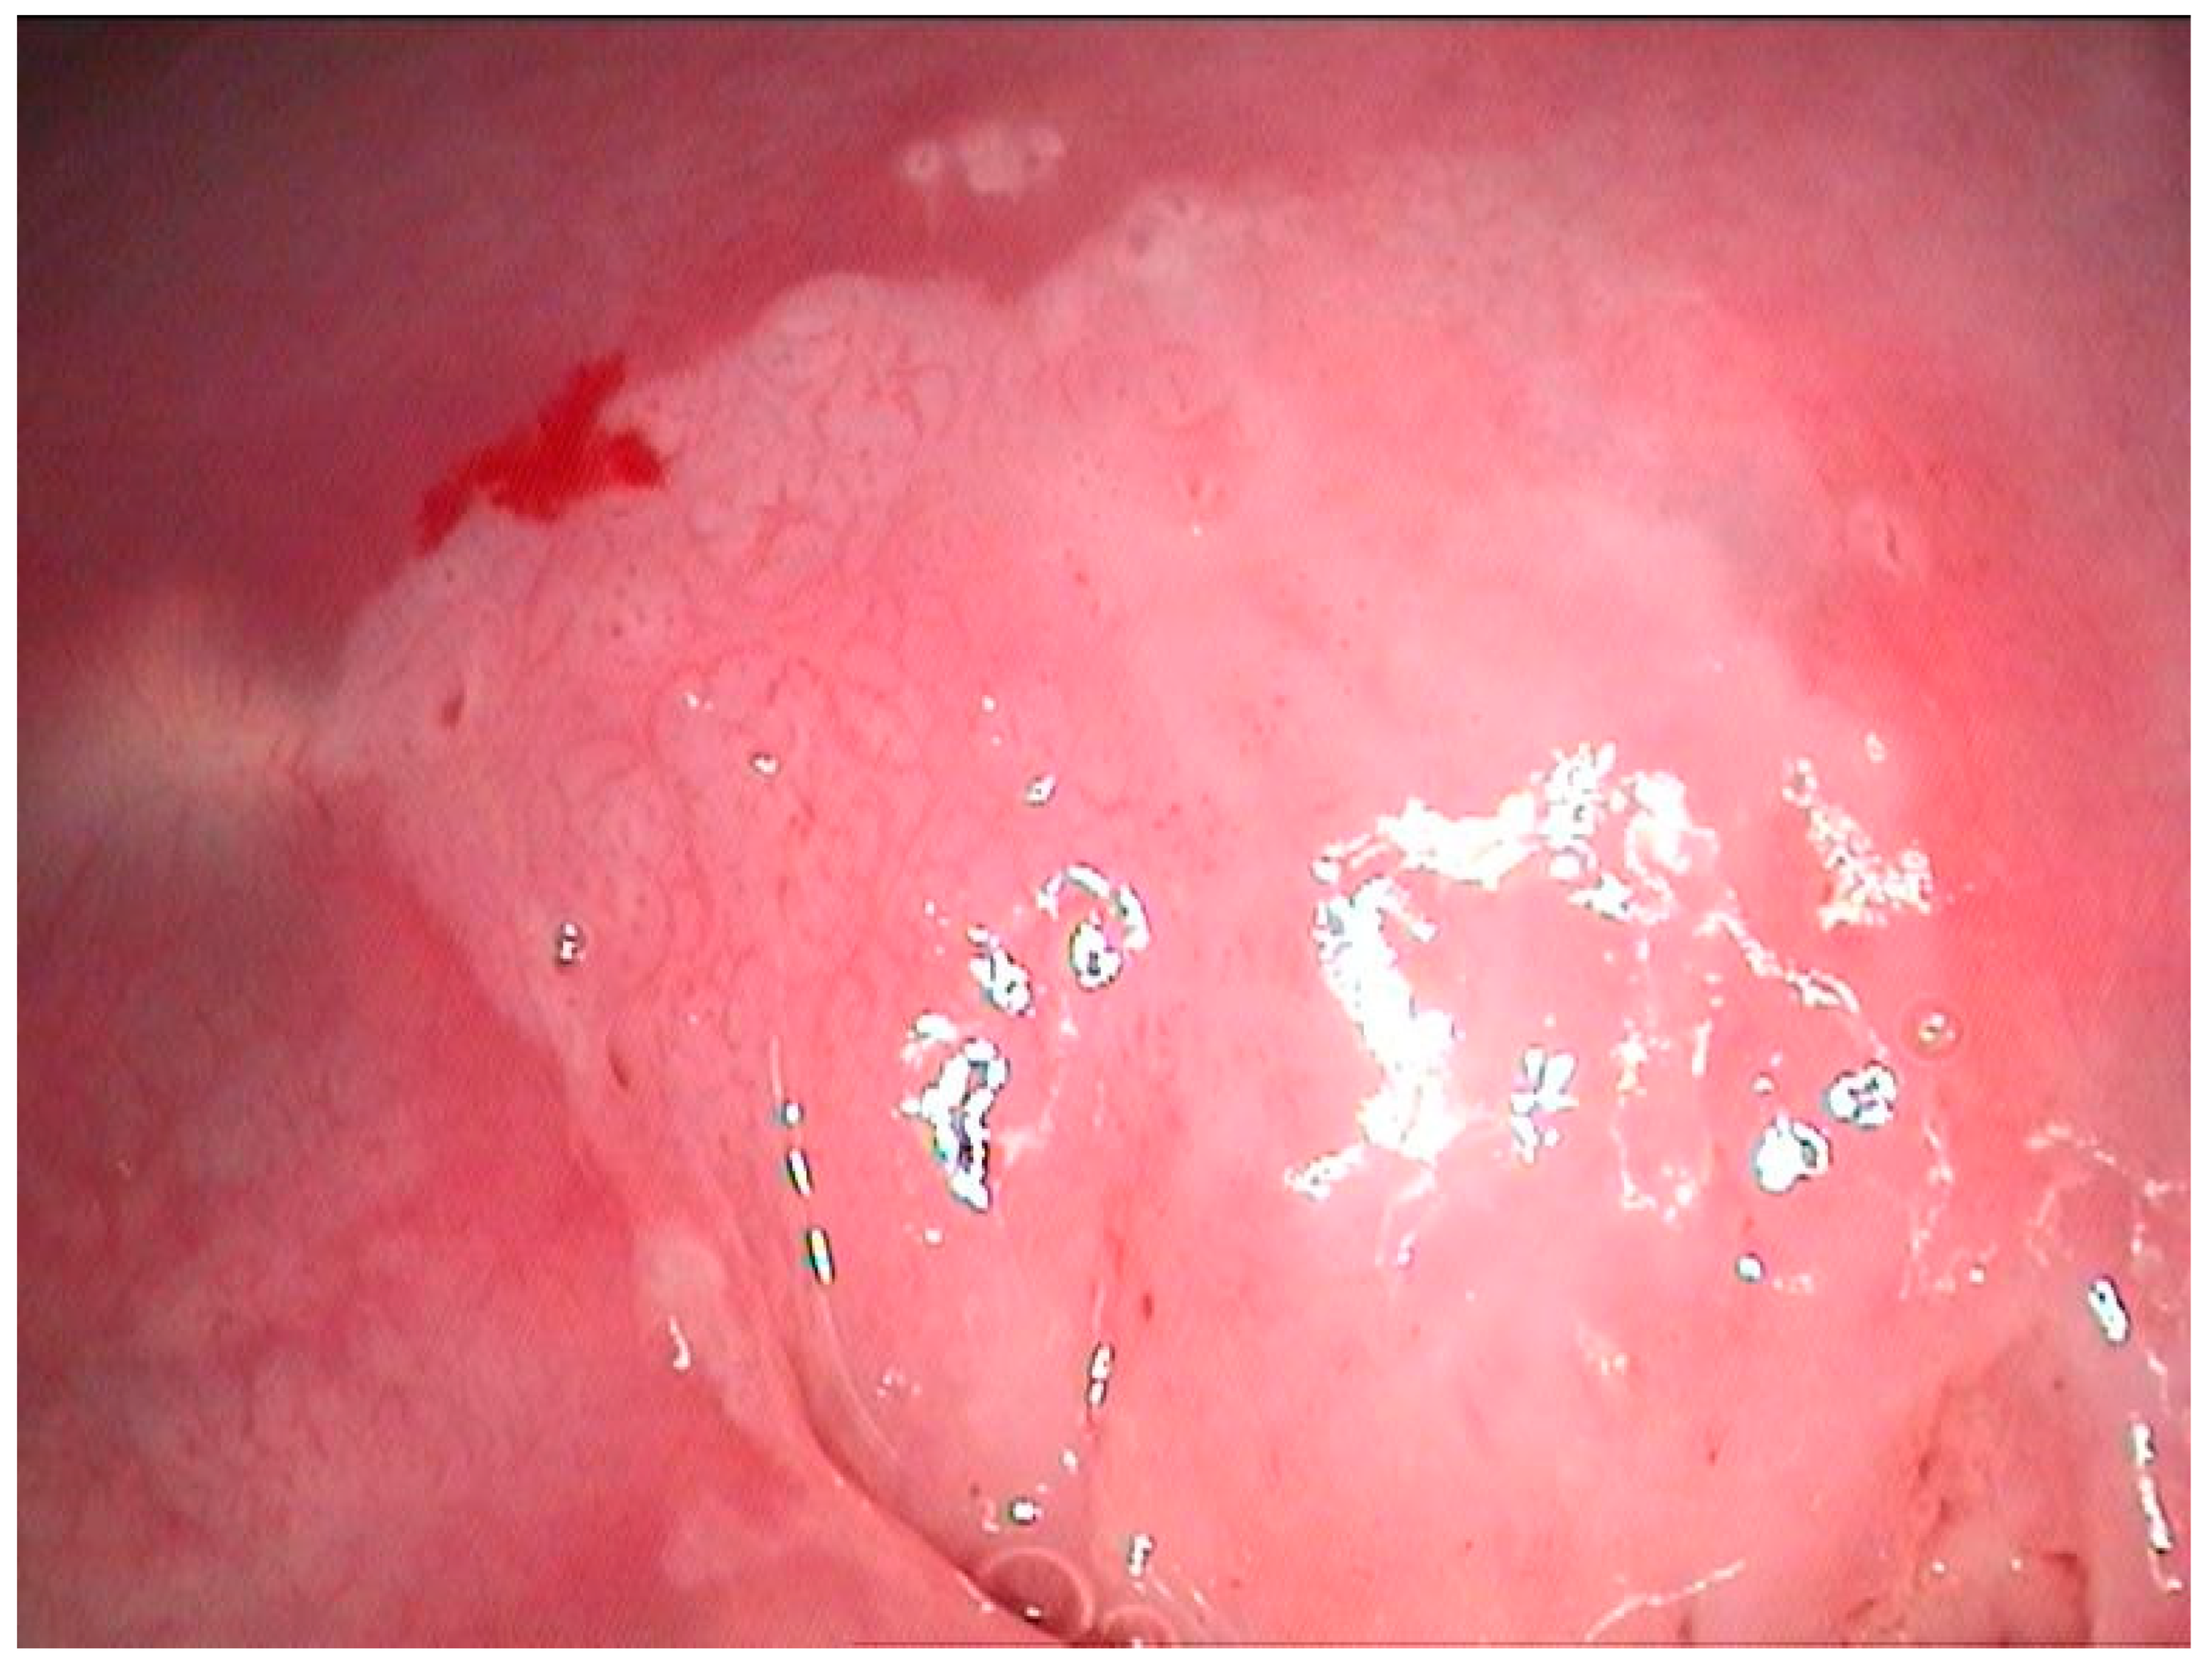

2.2. Clinical Examination